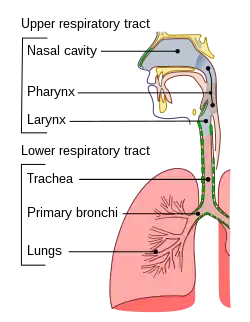

A traqueia (ou traquéia) é um tubo cartilaginoso que liga a laringe aos brônquios dos pulmões, permitindo a passagem do ar, e por isso está presente em quase todos os animais com pulmões. A traqueia se estende da laringe e se ramifica nos dois brônquios principais. No topo da traquéia, a cartilagem cricoide a liga à laringe. A traquéia é formada por vários anéis em forma de ferradura, unidos verticalmente por ligamentos sobrejacentes e pelo músculo traqueal em suas extremidades. A epiglote fecha a abertura da laringe durante a deglutição.

Estrutura

A traquéia é uma parte da árvore respiratória que é um canal para o ar passar em seu caminho para ou dos alvéolos dos pulmões. Isso transmite oxigênio para o corpo e remove o dióxido de carbono.[2][8]